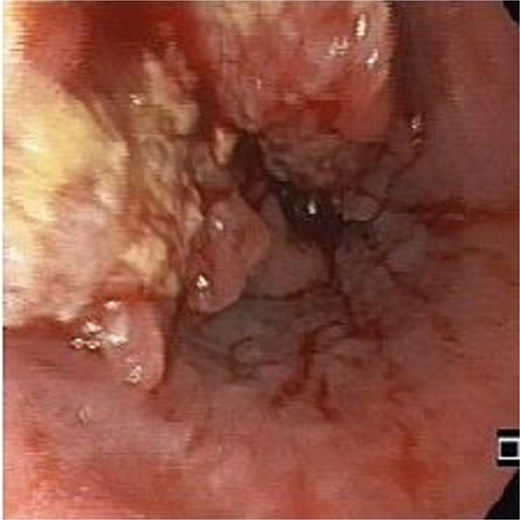

An 83-year-old male with progressive dysphagia and significant weight loss (15 kilograms in 3 months) was diagnosed with locally advanced upper thoracic esophageal squamous cell carcinoma, located 22–26 cm from the incisors, staged as T3N1M0 (Fig. 1). A PEG tube was inserted using the pull technique prior to initiating radiation (50.4 Gy) and chemotherapy (five cycles of Paclitaxel and Carboplatin). Three months after the initial diagnosis, he achieved a complete endoscopic and radiological response and regained the ability to eat orally.

Two months after completing chemoradiotherapy, a large abdominal wall mass measuring 6 x 6 cm with foul-smelling purulent discharge was noted adjacent to the PEG tube site (Fig. 2). Incisional biopsy of the mass was performed and revealed well-differentiated squamous cell carcinoma. According to these clinical and pathological findings, gastrostomy tract metastasis was suspected. A computed tomography (CT) scan of the chest and abdomen showed a 6.2 x 5.6 cm enhancing soft tissue mass in the anterior abdominal wall, centered around the gastrostomy site, extending deep to subcutaneous layer (Fig. 3). There was no evidence of distant metastasis. No mucosal lesion was observed on upper gastrointestinal endoscopy.